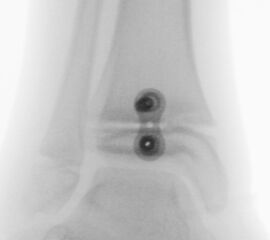

Knick-Senk-Platt-Fuß Korrektur mit dem Canalis Tarsi Spacer

In der Korrektur des schmerzhaften, aber flexiblen Knick-Senk-Fußes oder Plattfußes ist die Schraubenarthrorise mit einem Sinus tarsi oder besser bezeichnet als Canalis tarsi Spacer und alternativ mit einer Calcaneus-Stopp-Schraube seit vielen Jahren ein etabliertes Verfahren und führt zu einer kompletten Korrektur von flexiblen Knick- und Plattfuß-Fehlstellungen (Abb. 7). Die nötige Schnittlänge über dem Sinus tarsi beträgt für beide Verfahren 1 cm.

Abb. 7 a-e: Knick-Senk-Fuß prä- und postoperative Situation (a-b), ventrale und dorsale Ansicht (c-d). Laterale Ansicht des Hautschnittes über dem Sinus tarsi (e).